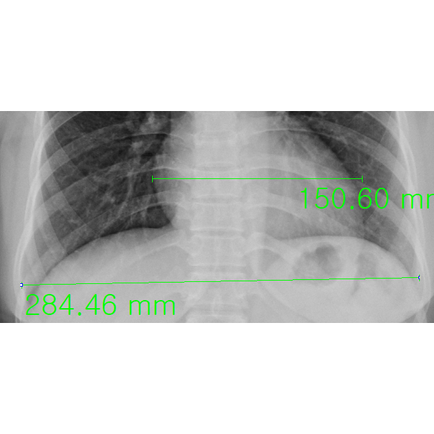

예약한 검진일 우연히 복통과 혈변의 증상 발생, 허혈성 의심... 기존 흉부 사진의 추적, 이상없었다고? - 동대문구 답십리, 전농동, 우리안애 우리안愛 내과